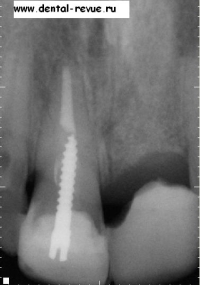

1. Прицельная рентгенограмма верхней челюсти (передние резцы) при первом обращении пациента (2004 год).

2. Прицельная рентгенограмма передних резцов верхней челюсти через 1,5 года: трещина корня 11, явный дефект костной ткани.

28. Диагностическая прицельная рентгенограмма переднего ряда верхней челюсти после операции перед установкой временных коронок.